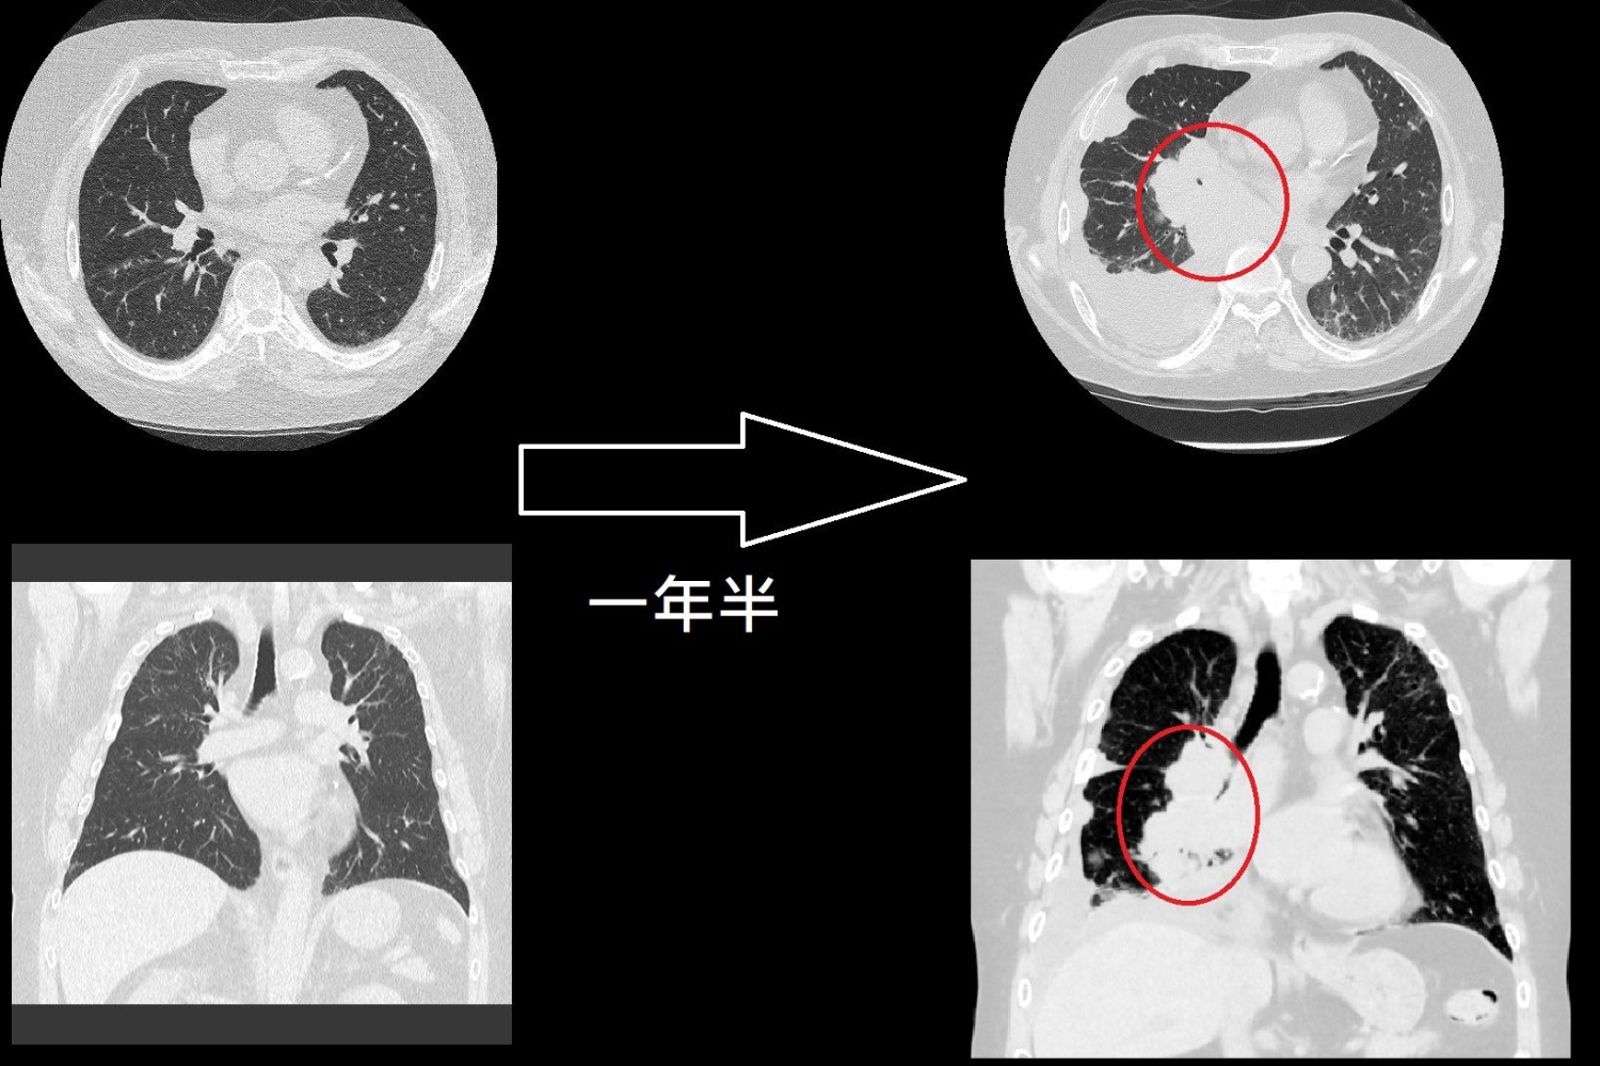

一名60歲的男子因為有慢性阻塞性肺病(COPD)而到醫院做檢查,1年半前做的電腦斷層並無任何異常,但男子近來因為氣喘而再次檢查,竟發現已經罹患肺癌,而且已經長出10公分大的腫瘤,已經是肺癌第4期了。

北市聯醫陽明院區胸腔內科醫師蘇一峰在臉書發文表示,這名60歲男子1年半前做了電腦斷層,當時的報告結果正常沒有任何肺結節。但是日前男子肺積水,會氣喘,照了X光疑似是肺癌,所以再安排一次電腦斷層,結果變成「肺癌第4期,而且腫瘤竟然有10公分大」。

蘇一峰感嘆,才短短1年半的時間,患者就從電腦斷層報告正常沒有任何結節,長到變成肺癌第期、腫瘤10公分,讓他覺得很難過,因為這名病患和病患的母親都是蘇一峰熟識已久的病患,「癌王小細胞癌真的太難了!」蘇一峰說,長大的速度真的太可怕。

蘇一峰說,肺小細胞肺癌只要營養足夠,30天長大1倍,所以1年半就能長大262144倍(2的18次方)。他說,「小細胞很難治療,時日不多了」,也讓他相當感概,「每個人都不知道自己還能活多久」。